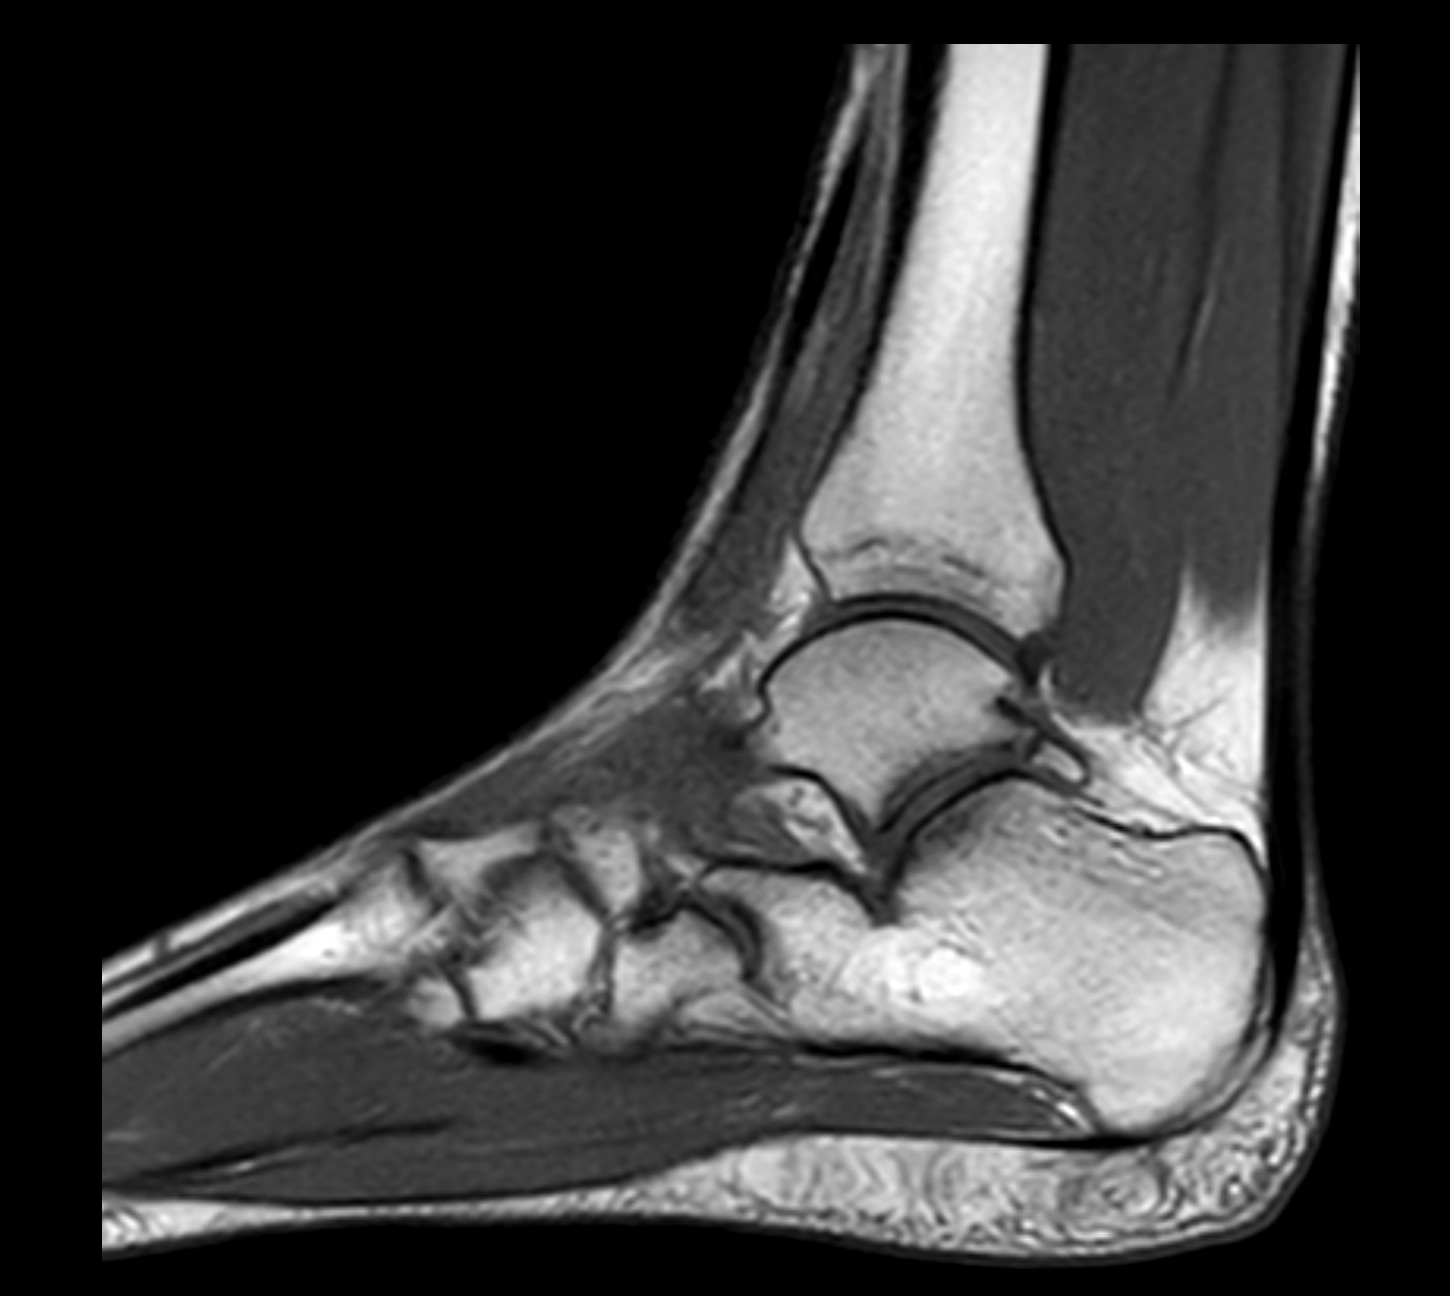

Med en magnetkameraundersökning (MR) av foten får du en högupplöst bild av fotens inre strukturer – inklusive skelett, ledbrosk, senor, ligament, ledkapslar och mjukdelar. Undersökningen är helt utan strålning och ger överlägsen detaljnivå jämfört med vanlig röntgen eller ultraljud, särskilt vid komplexa smärt- eller belastningsrelaterade problem i fot och häl.

MR ger en mycket tydlig bild av både benstruktur och mjukdelar, vilket gör undersökningen särskilt värdefull för att säkerställa diagnos inför behandling eller eventuell kirurgi.

En MR av foten är en avancerad, icke-invasiv undersökning som ger viktig information om orsaken till dina besvär. Undersökningen är särskilt värdefull vid symtom som inte gett svar med andra metoder eller inför beslut om behandling eller operation. MR fot tar cirka 30 minuter, är helt smärtfri och utan strålning. Bilderna granskas av erfarna röntgenläkare, och du får ett skriftligt utlåtande inom några dagar.